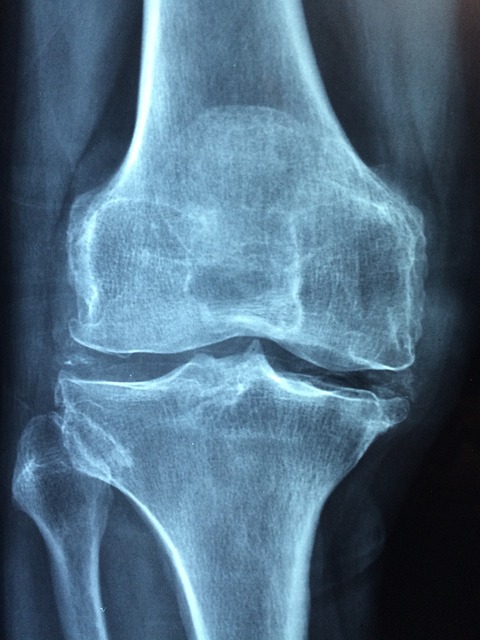

골다공증인지 아닌지 알고 싶다면 몇 가지 검사를 받으실 수 있습니다. 가장 대표적인 검사는 골밀도 검사 중에 이중에너지X선 흡수검사입니다. 가장 일반적이고 보편적인 검사입니다. 통 속에 들어가서 누워 계시면 골밀도가 측정되는 검사입니다. 우리가 일반 병원에서 행해지는 골밀도 검사는 이 검사 말고도 초음파, 단층 촬영과 같은 것들로 측정하는 경우들이 있습니다. 손이나 발 같은 것을 기계에 대고 찍는 검사들인데 간편하긴 하지만 정확도가 좀 떨어지고 추후에 보험을 적용하는 데 있어서 문제가 되기 때문에 검사를 하실 때에는 이중에너지 X선 흡수계측법이라는 방법으로 검사를 하시면 좋습니다. 흔히 덱사 검사라고 많이 부릅니다. 이 검사를 받아서 골다공증으로 진단이 된 경우에 환자분들이 가장 많이 하시는 질문이 '내가 골다공증 때문에 그동안 이렇게 허리가 많이 아팠구나 혹은 그것 때문에 내가 무릎이 많이 아팠구나' 이렇게 생각하시는 분들이 많이 계십니다. 그런데 실제로 골다공증은 통증이 있는 병이 아닙니다. 골다공증은 아픈 것은 아니지만 뼈가 약해져서 뼈 안이 숭숭 비게 되면서 넘어지거나 부딪혔을 때 잘 부러지기 쉬운 상태가 되는 것을 골다공증이라고 합니다.